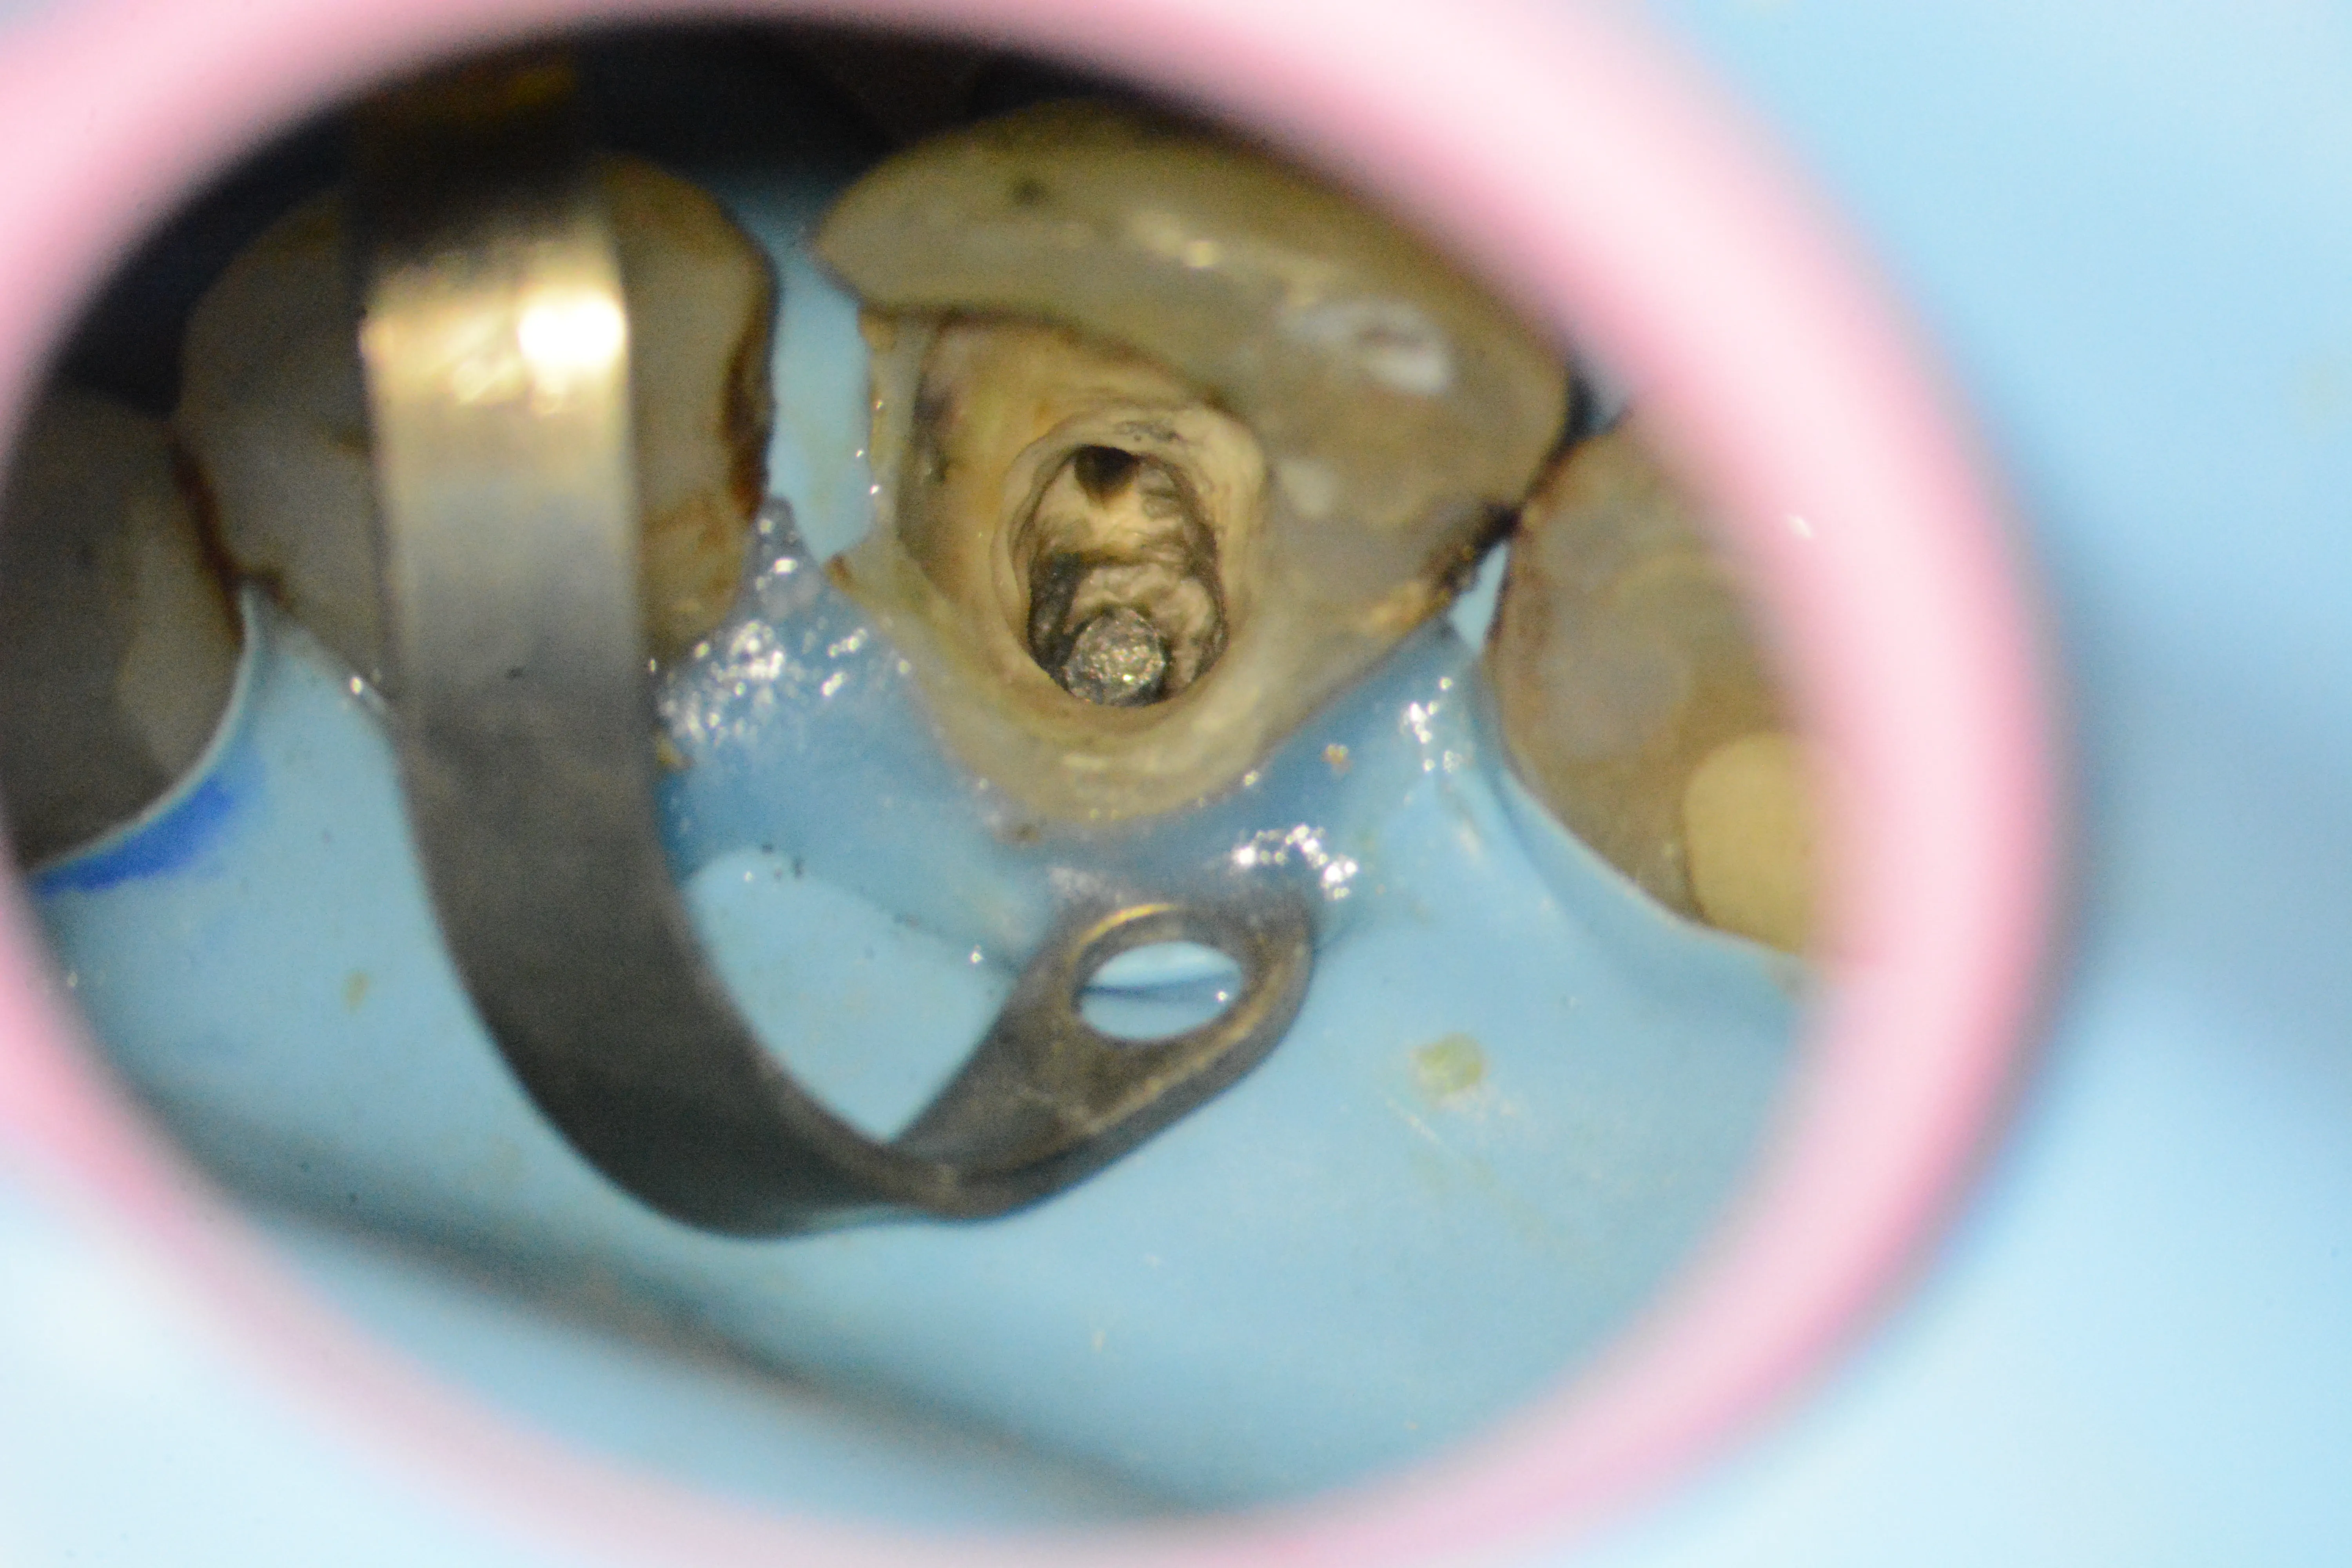

6 – Aspectul frezei din canalul radicular

7 – Expunerea frezei pentru a încerca mobilizarea ei